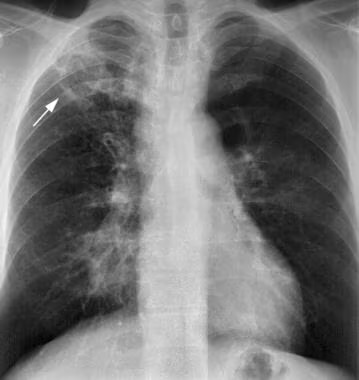

Обследование проводится в прямой (переднезадней) и боковой проекциях грудной клетки, при необходимости — с прицельной съёмкой верхушек лёгких. Визуализируются преимущественно прямые признаки: множественные очаги уплотнения в лёгочной ткани, преимущественно в верхних отделах, с характерными особенностями формы и распределения. Цель исследования — выявление локализации, количества, размеров и структурных особенностей туберкулёзных очагов, а также оценка наличия сопутствующих изменений.

Рентгенография выявляет следующие признаки очагового туберкулёза лёгких:

Наличие множественных малых очагов (2–5 мм) округлой или неправильной формы с неравномерной интенсивностью тени, чаще в субапикальных и верхнедолевых отделах.

Тенденция к группировке очагов, образующих конгломераты с нечёткими, размытыми контурами, особенно на фоне фиброзно-склеротических изменений.

Участки с просветлениями или кальцинатами, свидетельствующими о давности процесса или очаговом обызвествлении.

Местное обеднение сосудистого рисунка и умеренная деформация лёгочного поля в зоне поражения.

Перифокальный интерстициальный отёк или уплотнение, особенно в фазе инфильтрации.

При прогрессирующем течении — формирование небольших полостей распада с неравномерными внутренними стенками.